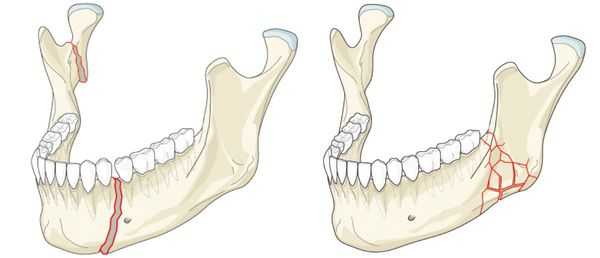

Механизм смещения отломков нижней челюсти. Смещение отломков под влиянием мышц.

Смещение отломков происходит вследствие продолжающегося действия приложенной силы, под влиянием собственной их тяжести и в силу сокращения (тяги) прикрепленных к отломку мышц. Последний фактор является основным при переломе нижней челюсти, так как мышцы действуют постоянно и разнонаправленно.

Рис. 12.5. Возможные переломы нижней челюсти вследствие перегиба (по Вассмунду).

а — прямой перелом тела нижней челюсти; б — непрямой перелом нижней челюсти в области мыщелкового отростка или угла; в — непрямой перелом нижней челюсти в области подбородка; г — непрямой перелом нижней челюсти в области ее шейки и бокового отдела тела; д — прямой перелом нижней челюсти в области угла и непрямой в боковом отделе подбородочной области.

Таким образом, передняя группа мышц смещает концы длинного отломка вниз. Челюстно-подъязычная мышца поворачивает его вдоль продольной оси, наклоняя зубы в оральную сторону. Латеральная и в меньшей степени медиальная крыловидные мышцы смещают больший отломок в сторону перелома. Жевательная и височная мышцы поднимают меньший отломок кверху. Кроме того, жевательная мышца смещает основание малого отломка кнаружи, альвеолярную часть с зубами наклоняя орально. Латеральная крыловидная мышца на стороне малого отломка смещает его несколько кнутри. При этом смещение отломков нижней челюсти происходит вверх, вниз, кнутри, кнаружи. Возможно смещение их в горизонтальной плоскости (по длине), когда концы фрагментов соприкасаются своими боковыми поверхностями. Это чаще встречается при косых переломах или в ситуациях, когда боковое смещение превышает поперечное сечение сломанного участка кости. При переломах мыщелкового отростка сместившиеся отломки чаще располагаются под углом друг к другу. В клинической практике указанные варианты смещения отломков сочетаются между собой.